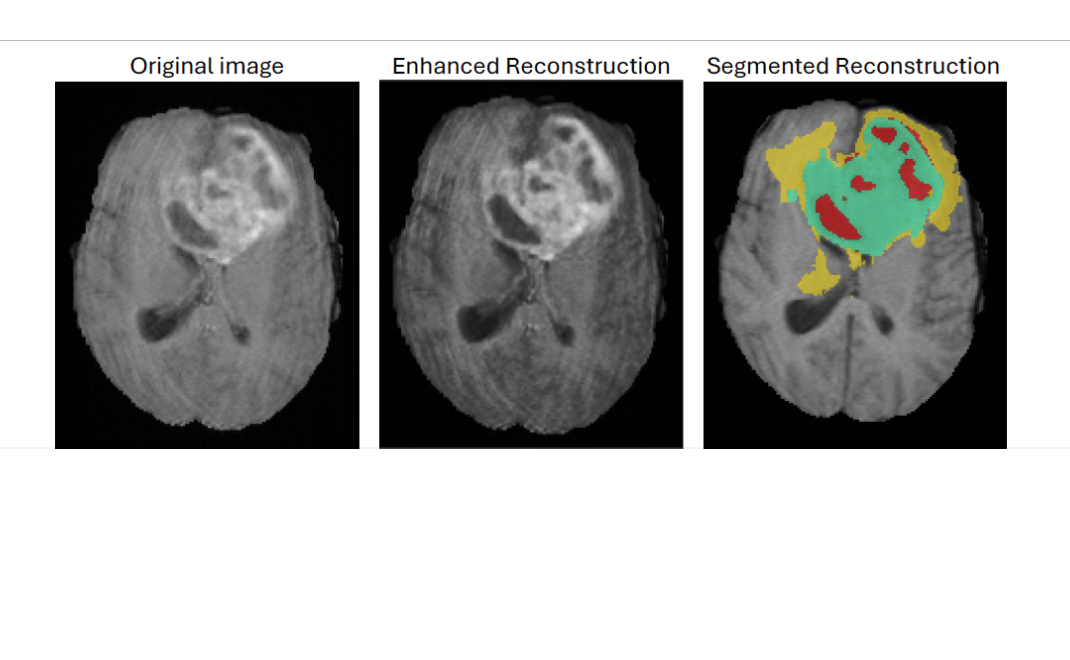

Filling the Blind Spots in Brain Imaging

Meet Sarah Anjum, a Computer Science PhD student using WAVE HPC's GPU resources to develop AI models that reconstruct full 3D MRI brain scans — enabling radiologists to detect tumors and abnormalities with greater precision than ever before.